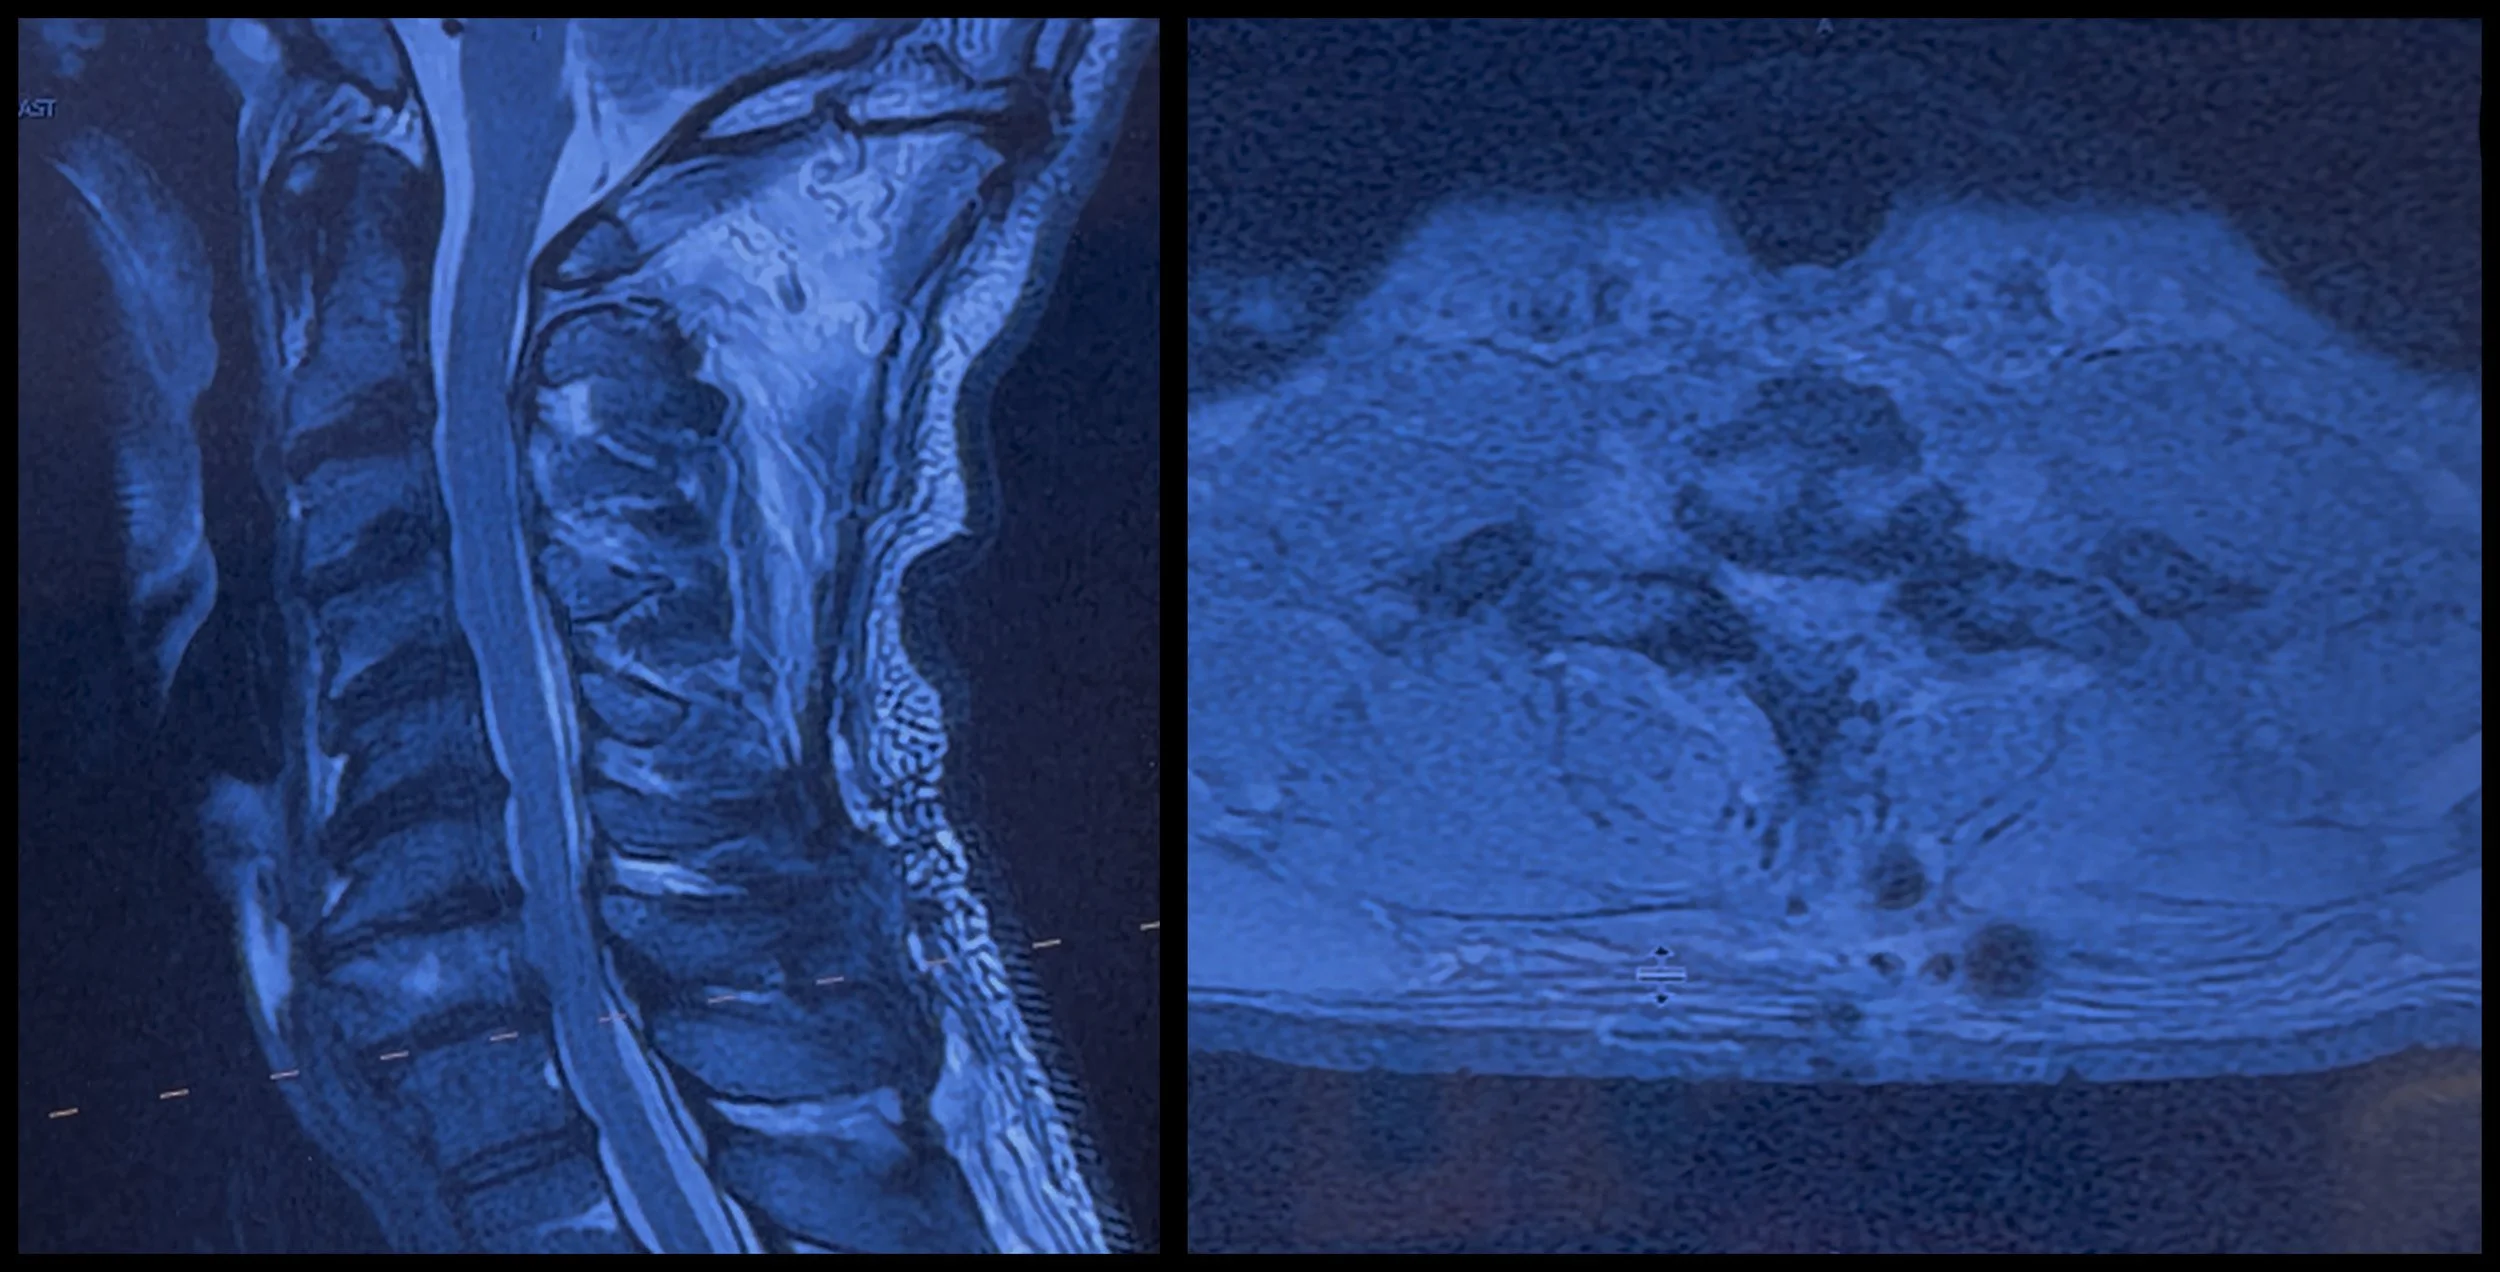

Desde entonces he reunido tomografías, estudios de imagen y documentación médica para poder explicar con precisión lo que está ocurriendo. Estoy compartiendo algunas de esas imágenes aquí para que puedan verlo de manera directa.

Las cirugías que me realizaron hasta ahora en esa área fueron:

Discectomía cervical anterior con fusión (ACDF)

Niveles fusionados en el cuello: C6–C7 y C7–T1

Descompresión y fusión lumbar

Nivel fusionado en la zona lumbar: L5–S1

El dolor que estoy experimentando es real y estructural. El hardware colocado en mi columna durante las cirugías anteriores está estable. Sin embargo, cuando realizo ciertos movimientos, el titanio presiona contra el hueso circundante. Esa presión, combinada con inflamación, está afectando nervios cercanos.

Esto explica el dolor persistente y los síntomas neurológicos, y también por qué la recuperación ha sido más lenta y compleja de lo esperado.

Aquí pueden ver el antes y el después de la cirugía, así como mi estado actual de recuperación.

Durante el último año he pasado por múltiples cirugías de columna y estudios de seguimiento. Recientemente reuní varias de mis tomografías y radiografías de distintos momentos de este proceso. En ellas se pueden ver el hardware, las fusiones y los cambios estructurales que explican por qué este ha sido un recorrido médico largo y continuo. Comparto algunas de esas imágenes aquí simplemente para mostrar que esto es real, está documentado y está siendo tratado activamente.

A mediados de diciembre me realizaron una tomografía de control de la columna cervical. Los resultados muestran que la recuperación está avanzando, pero todavía hay cambios en formación en mi cuello que requieren tratamiento continuo. Mis médicos han sido muy claros en que este proceso no termina aquí.